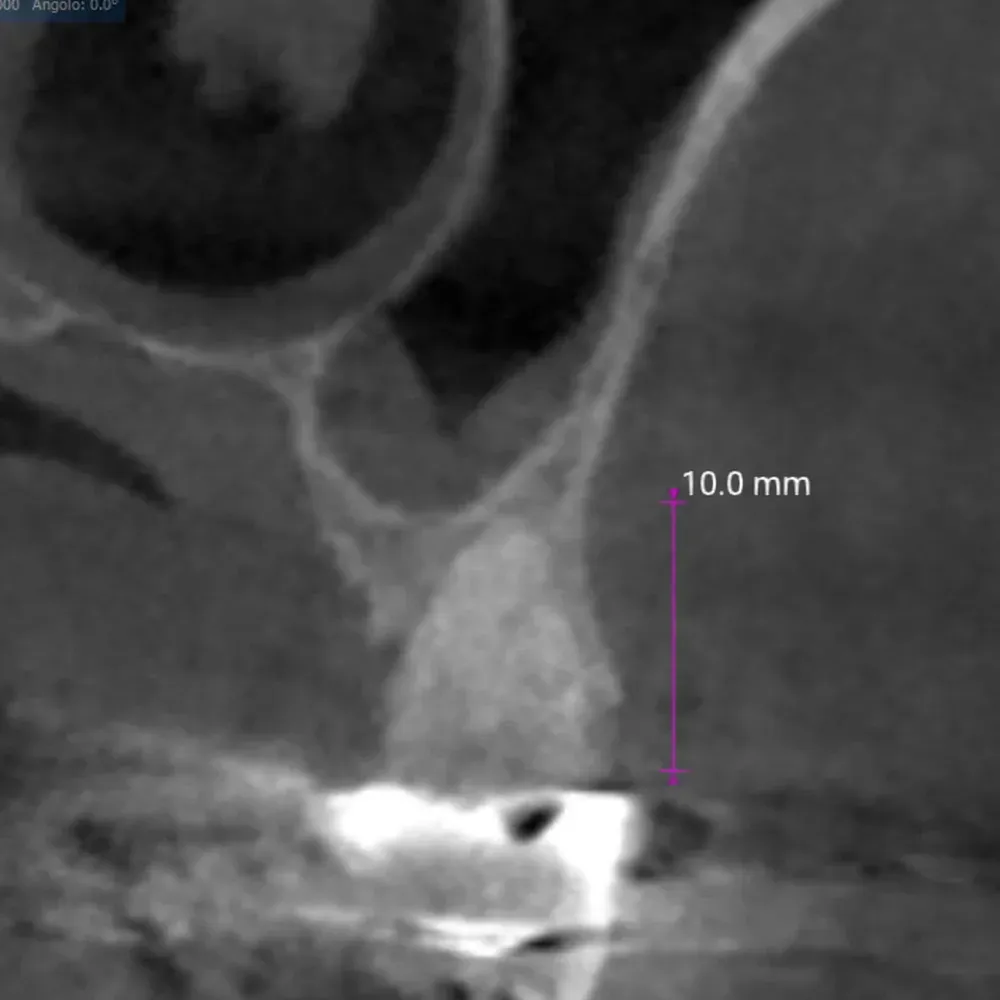

Sezione espansore sito 2.5

Espansore in posizione 2.5 con sollevamento della corticale del pavimento del seno